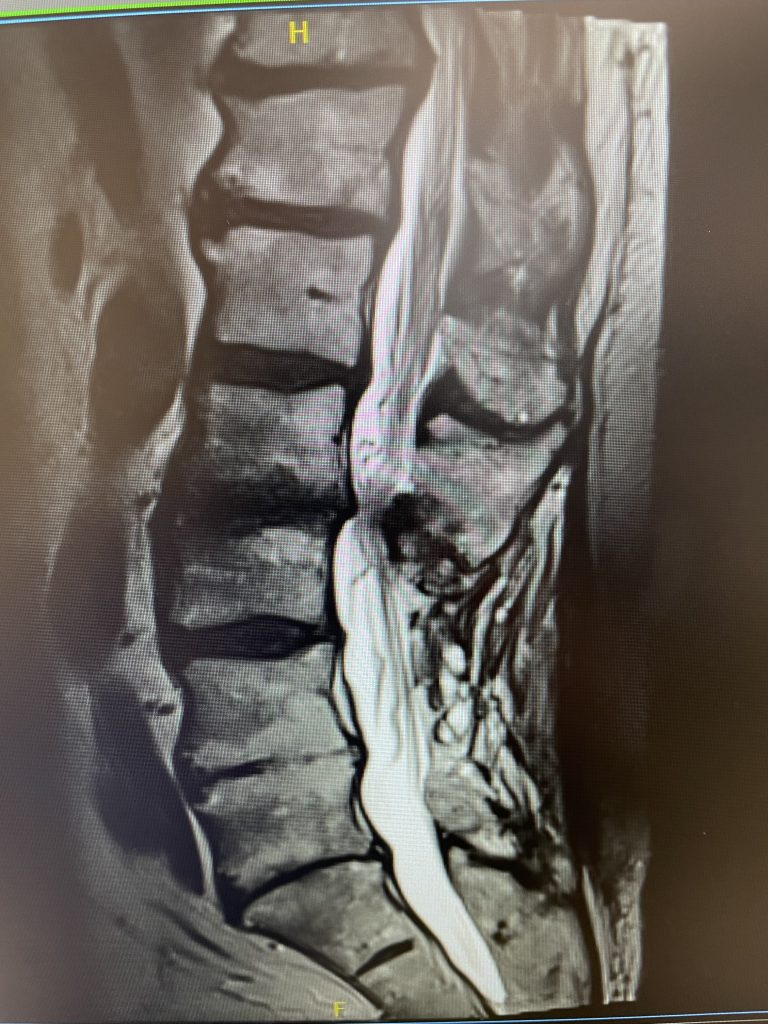

IMG 4749 scaled

A 69-year-old male presents with chronic low back pain that seems to improve with sitting. The patient had had a prior laminectomy for severe stenosis and in situ fusion five years prior which means that we used bone graft to perform the fusion but no instrumentation. He had done well. Over the last year or so he developed low back pain but no leg pain. The patient had tried all means of conservative management including physical therapy, chiropractic care, acupuncture and epidural injections. Neurologically he was intact. MRI revealed significant stenosis at L2-3 above his prior laminectomy and fusion (Fig 1). We discussed options including surgery. One of the problems we face is a patient with severe stenosis that has severe low back pain with no leg pain. This is particularly challenging when the back pain goes away in flexion or sitting. The quandary is that anecdotally patients with these specific symptoms do tend to improve their back pain after laminectomy, although there are no good studies to support this. Patients with classic neurogenic claudication with pain down their legs when they walk and improved when they sit have a better chance of success. Subjecting a patient to laminectomy for just back pain in the face of having prior surgery puts the patient at risk for not only a potential dural leak because of scarring, but also there may be less of a chance of relieving the back pain than if the patient has leg symptoms. After a discussion, since the patient for the most part is able to manage with conservative treatment modalities is just wait and see over the next three months.